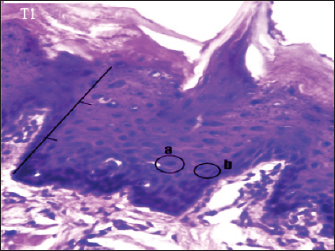

Histopathologically described the rat tongue epithelium in the positive control group (C+) showed that the cells had dysplasia. Cells appear irregular stratification and loss of basal cell polarity, and there are variations in cell size and nucleus size. Cells and nuclei in the granulosum layer also undergo variations in shape, and there is a hyperchromatic nucleus. The ratio between the nucleus and the cytoplasm also increases. The epithelial change of the tongue toward dysplasia is about two-thirds the thickness of the epithelium (Fig. 1).

Fig. 1. Histopathological description of the rat tongue epithelium in the positive control group (C+), microscope at ×400. (a) Hyperchromatic nucleus; (b) the size of the nucleus increases so that the ratio between the nucleus and the cytoplasm increases.

Fig. 3. Histopathological description of the rat tongue epithelium in the T1 group, microscope at ×400. (a) the ratio between the nucleus and the cytoplasm increases, with a hyperchromatic nucleus; (b) the shape of the nucleus showing anisonucleus.